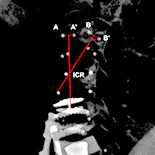

Five freshly frozen, unembalmed whole human cadavers were used including 3 males and 2 females with a mean age of 51±8 years. After evaluating the intact spine for range of motion (ROM), sagittal alignment and instantaneous center of rotation (ICR), each cadaver underwent 4 consecutive surgeries: 2-level artificial disc replacement (ADR) from C4 to C6 (ADR surgery); 2-level ACDF from C4 to C6 (ACDF surgery); hybrid C4-5 ACDF and C5-6 ADR (ACDF+ADR surgery); and hybrid C4-5 ADR and C5-6 ACDF (ADR+ACDF surgery). The ROM and ICR of adjacent intact segments (C3-4; C6-7), and whole sagittal alignment were revaluated.

Two-level ACDF resulted in increased ROM at C3-4 and C6-7 compared with intact spine. ROM was significantly different to intact spine using ACDF surgery at C3-C4 and C6-C7 and ROM was increased with ACDF+ADR surgery at C6-C7 (all P<0.05). No improvement in sagittal alignment was observed with any approach. The localization of the ICR shifted upwards and anteriorly at C3-C4 after reconstruction. ICR changes at C3-C4 were greatest for ADR+ACDF surgery and were significantly different to ACDF surgery (P<0.05), but not between ADR surgery and ACDF+ADR surgery. At C6-C7, the ICR was more posterior and superior than in the intact condition. The greatest change in ICR was observed in ACDF surgery at the C6-C7 level, significantly different from the other groups (P<0.05).